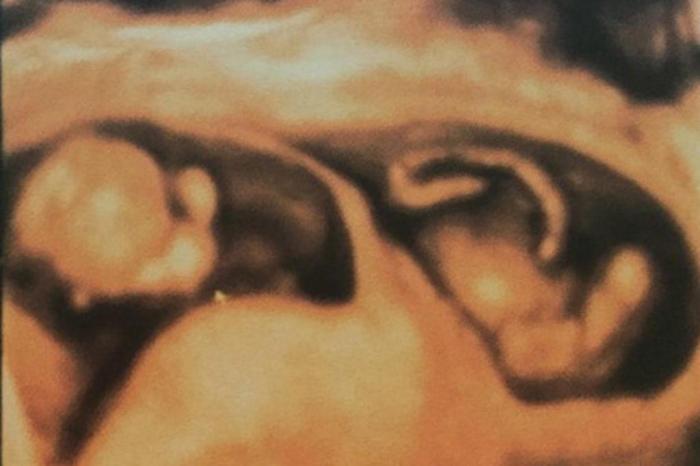

Atriz está grávida de gêmeos e postou foto do exame em rede social.

Uma gravidez planejada e que chegou um tanto rápido tem agitado os dias de Luana Piovani e sua família no Rio de Janeiro. Nesta quarta-feira, a atriz mostrou o ultrassom dos gêmeos no Instagram e babou pelos filhos caçulas que vêm por aí. Apesar de não ter descoberto o sexo das crianças ainda, ela não deixa a expectativa passar sobre o nascimento dos filhos.

"Um bebezuco mostrando a cabecinha e o outro bebezuco exibindo a pancinha! Obrigado, Senhor!", escreveu na legenda da rede social, toda empolgada com os bebês na web.